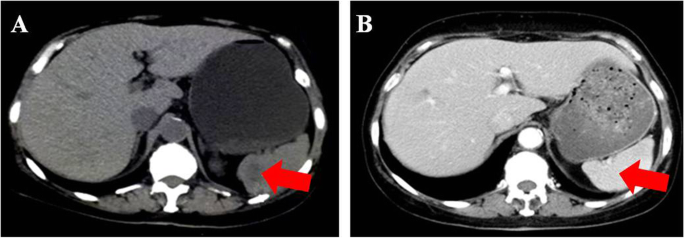

Patient 2 was a 61-year-old female who presented with intermittent lower abdominal pain with a large cystic and solid mass in the right ovary by ultrasonography. She underwent the cytoreduction to no macroscopic residual disease (total abdominal hysterectomy, bilateral salpingo-oophorectomy, omentectomy, appendectomy, bilateral pelvic and para-aortic lymph node dissection, multi-point biopsy of peritoneal) and was diagnosed with stage IIIa2 ovarian carcinosarcoma by pathologic staging. The patient strongly objected to receiving adjuvant chemotherapy due to personal preference. Thirteen months after surgery, she experienced recurrence. Accompanied by an increasing serum CA125 level (94.79 U/ml), there were multiple low-density shadows (the largest shadow was approximately 2.5 cm in size) in the spleen (Fig. 3a), and the liver was thought to have metastatic lesions, with a cystic mass on the right side of the pelvic cavity that was regarded as a lymphatic cyst by CT. Meanwhile, genetic testing showed that she harbored gBRCAwt disease. The patient refused chemotherapy again and took olaparib at a daily oral dose of 300 mg twice per day. She suffered mild arthralgia and anemia in the first month. Seven months after taking the medicine, the serum CA125 level decreased to 4.01 U/ml (Fig. 1), and CT showed that multiple metastases in the spleen disappeared (Fig. 3b). Multiple nodules in the liver were the same as before, and the largest nodule was approximately 1.96 × 1.66 cm in size.